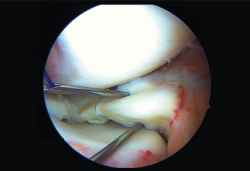

Un varón de 25 años sufrió una torsión de la rodilla derecha 2 meses antes. Presentaba clínica de bloqueo articular y derrame. Se realiza una reparación de la lesión meniscal con forma de asa de cubo, menisco medial, puntos de fuera-dentro y todo dentro. Visión desde el portal medial.

Las roturas del menisco con asa de cubo comprenden casi el 10% de todas las roturas meniscales, afectando generalmente a población joven masculina. El desplazamiento del segmento libre puede ocasionar dolor y bloqueos, lo que requiere reducción y tratamiento quirúrgico. La reparación siempre debe intentarse. Las opciones para el tratamiento quirúrgico incluyen desde meniscectomía parcial a reparación realizando técnica de fuera-dentro, todo dentro, dentro a fuera o una combinación.

El diagnóstico y la reparación temprana de los desgarros en asa de cubo es muy importante. La falta de tratamiento o el retraso puede conllevar un menor éxito de la reparación, mayor dificultad o imposibilidad, resultando en una meniscectomía con una progresión más temprana de osteoartritis.